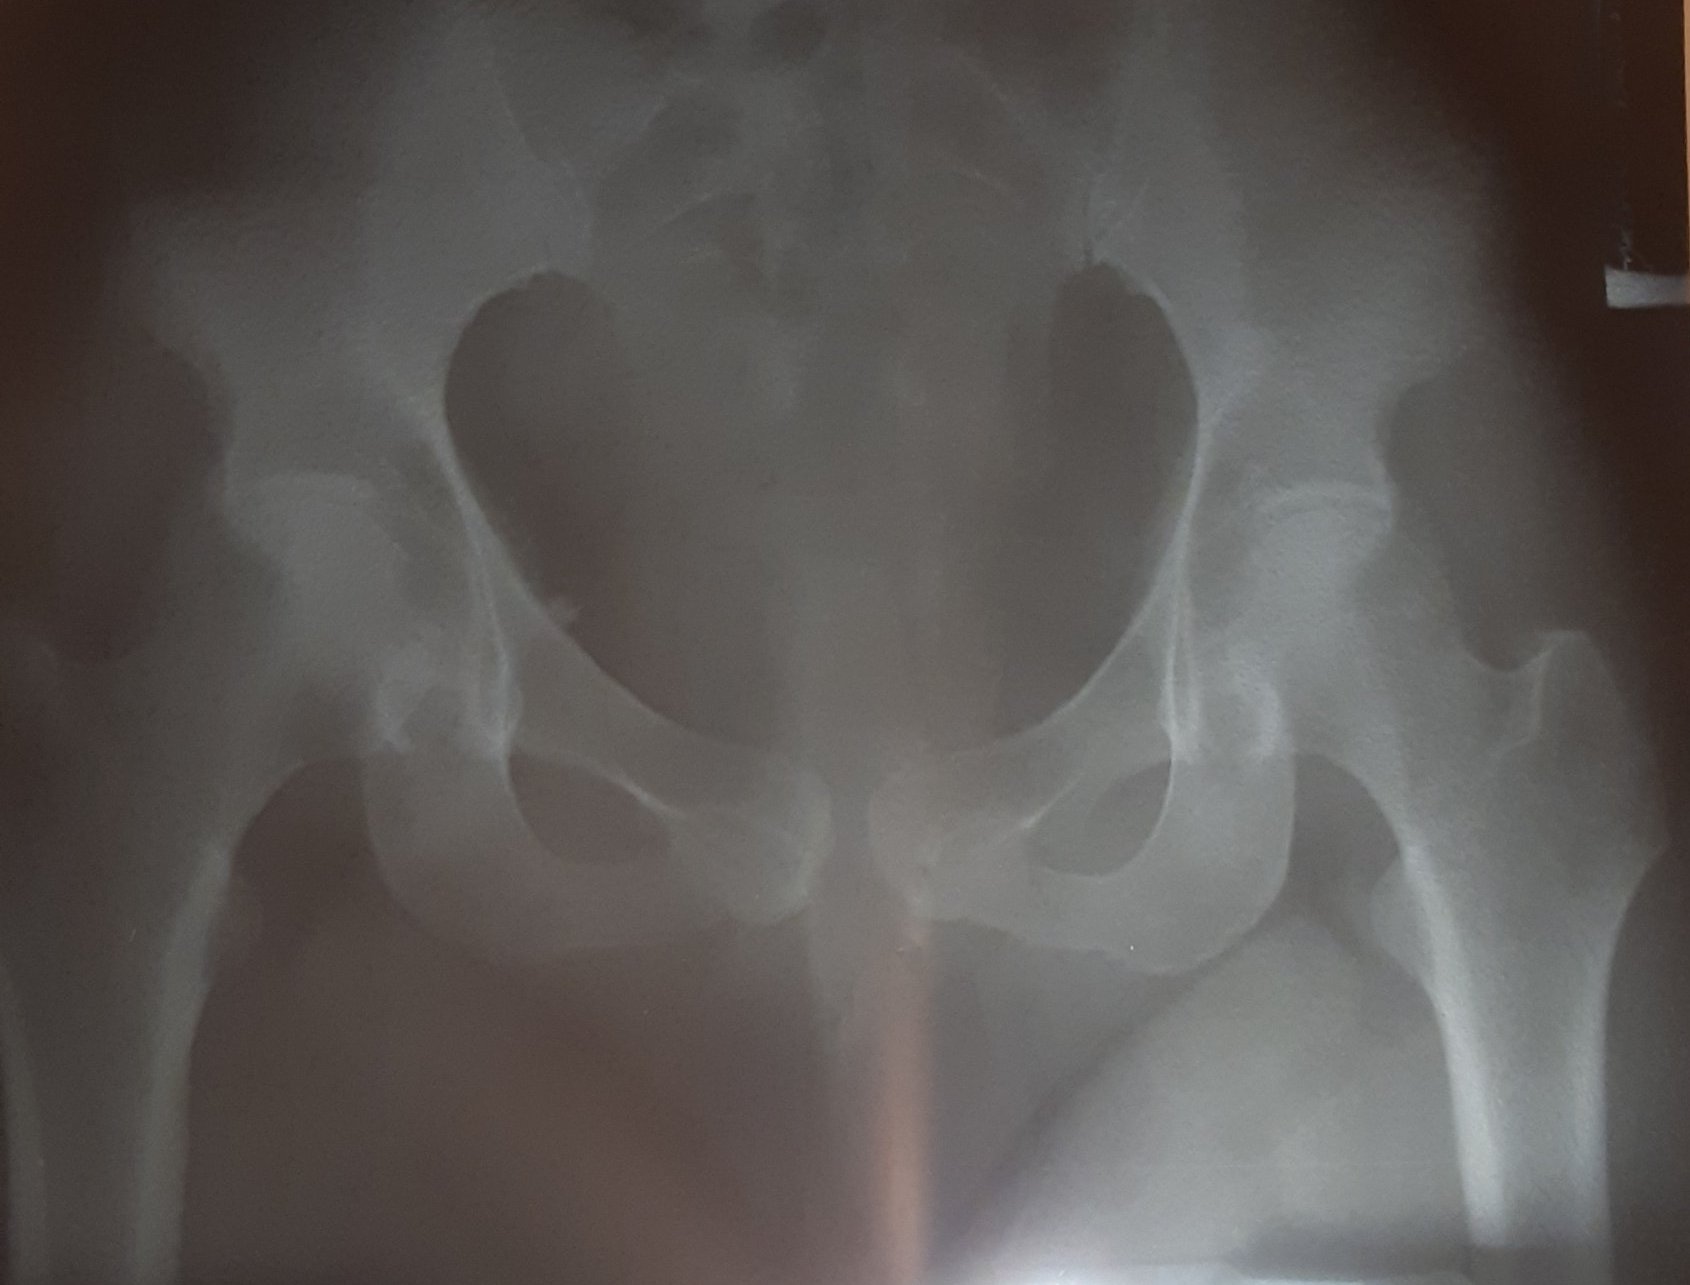

Плоскостъпието може да доведе до болки в кръста при деца поради натоварването на гъвкавите стави. За предотвратяване на това е необходим специализиран преглед и оценка за ортопедични стелки както за ежедневно носене, така и за тренировки. Освен това е важно да се консултирате с ортопед и да направите образни изследвания, ако болката не отшуми след 3-5 дни, тъй като може да има риск от сколиоза.